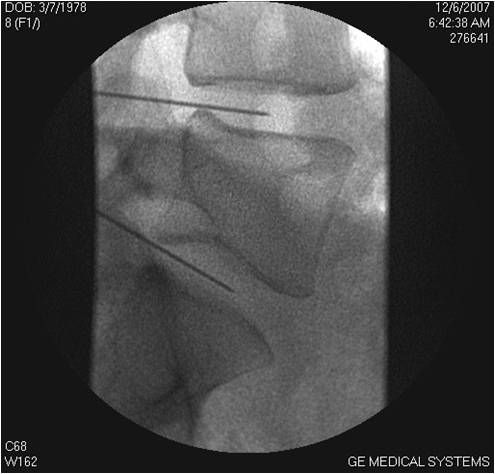

Le procedure che utilizzo, dall'ozonoterapia ai trattamenti con monociti autologhi, dall'acido ialuronico di alta fascia all'idrogel fino alle procedure TC-guidate, non bruciano nessun ponte terapeutico futuro ma lo garantiscono.

• Chirurgia vertebrale

• Ossigeno-ozono terapia